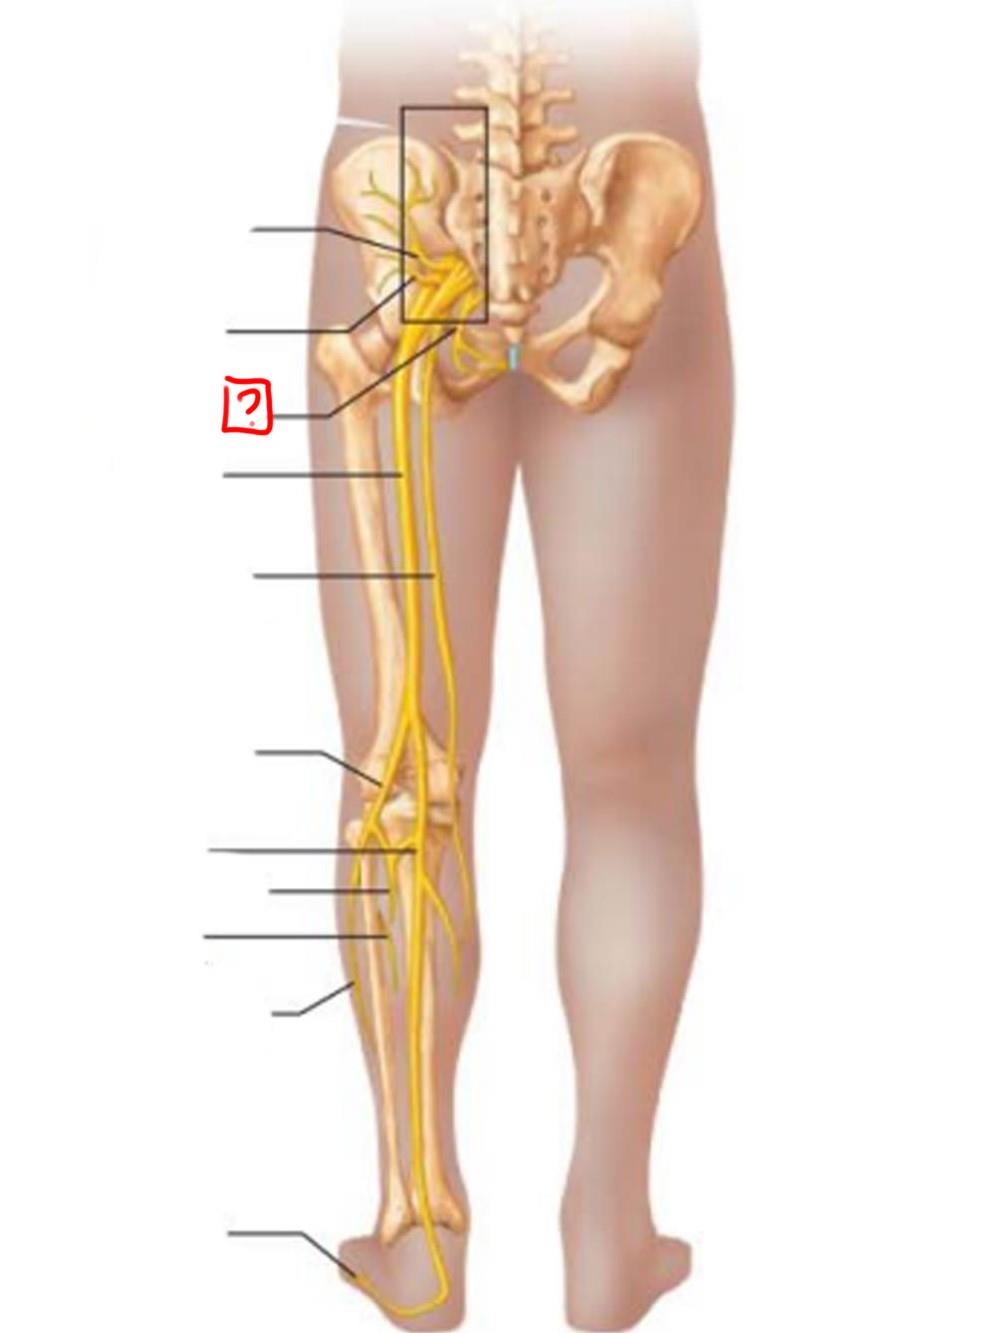

obturator

femoral

lumbosacral trunk

iliohypogastric

ilioinguinal

femoral

lateral femoral cutaneous

obturator

anterior femoral cutaneous

saphenous

superior gluteal

inferior gluteal

pudendal

sciatic

posterior femoral cutaneous

common fibular

tibial nerve

sural (cut)

deep fibular

superficial fibular

plantar branches

superior gluteal

lumbosacral trunk

inferior gluteal

common fibular

tibial

posterior femoral cutaneous